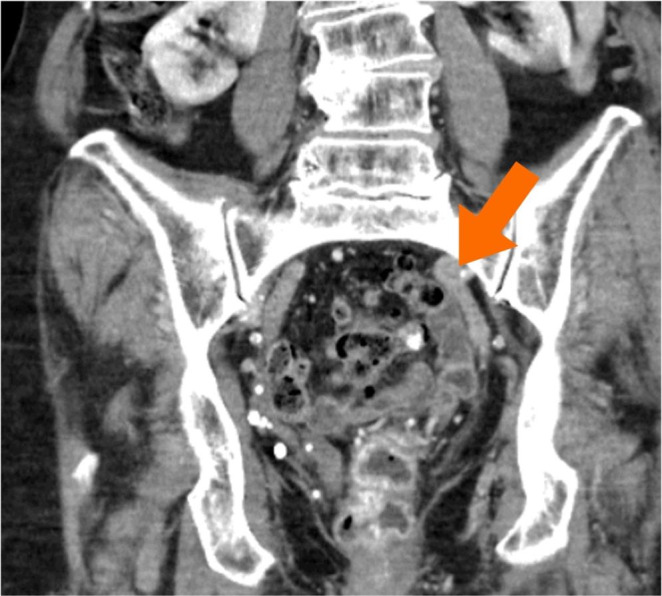

Materials and methods: In this video an 86-year-old woman with ODS and POP, suffering from a dolichocolon with rectal intussusception, an apical prolapse after total hysterectomy 1990, and occasional stress urinary incontinence underwent interdisciplinary laparoscopic surgery. A tubular anterior rectal and sigmoid resection with suture rectopexy as in a resection rectopexy (RRP) was combined with a sacrocolpopexy (SCP) using a synthetic mesh.

Abstract Image